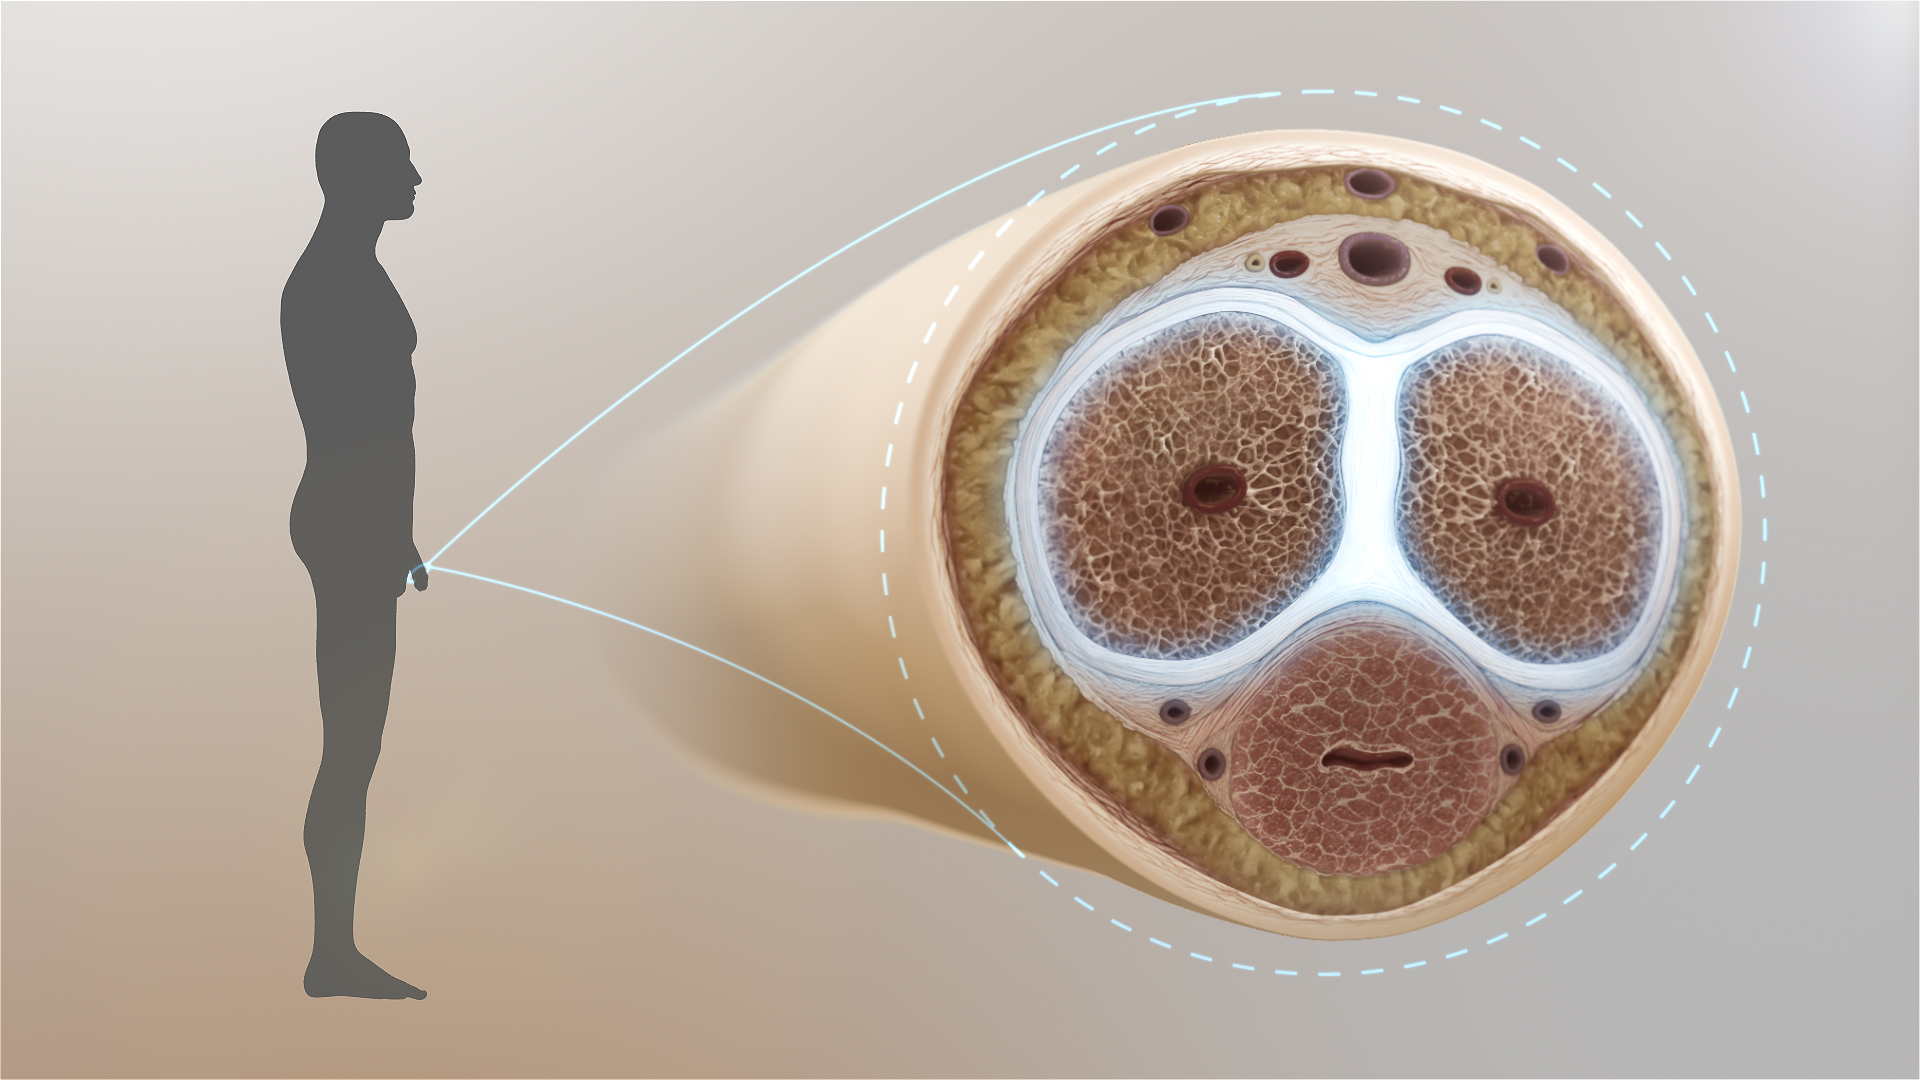

Το ανδρικό μόριο μπορεί να μην έχει οστά, παρ΄ολα αυτά μπορεί να υποστεί κάταγμα στους κυλινδρικούς άξονες που διοχετεύουν το αίμα στην περιοχή κατά τη στύση.

Εάν αυτοί οι άξονες βρίσκονται σε κάμψη την ώρα της στύσης μπορεί να προκληθεί ρήξη και το πέος να γεμίσει με αίμα, ένα πρόβλημα που αν δεν αντιμετωπιστεί άμεσα μπορεί να οδηγήσει σε μόνιμη δυσμορφία ή η απώλεια σεξουαλικής λειτουργίας.

Σύμφωνα με το Ινστιτούτο Μελέτης Ουρολογικών Παθήσεων (ΙΜΟΠ), το ανδρικό μόριο, παρ’ ότι ευκίνητο σε ηρεμία (χάλαση), γίνεται σκληρό κι ευθύ με τον ερωτικό ερεθισμό, αφού γεμίζει με αίμα. Και τα δύο αυτά χαρακτηριστικά είναι απαραίτητα για να επιτελέσει τη λειτουργία για την οποία υπάρχει: τη σεξουαλική πράξη.

Σε σπάνιες περιπτώσεις, ο χιτώνας που περιβάλει τους κυλινδρικούς άξονες μπορεί να σχιστεί σε μεγάλο βαθμό κατά τη διάρκεια σεξουαλικής επαφής (συνήθως συμβαίνει σε συγκεκριμένη στάση, όπου η σύντροφος με το βάρος της πιέζει και συνθλίβει το πέος) και να προκληθεί το καλούμενο κάταγμα πέους.

Πρόκειται για μια οδυνηρή εμπειρία, αφού συνοδεύεται από εντονότατο πόνο και μεγάλο αιμάτωμα του πέους. Το κάταγμα του πέους είναι επείγουσα χειρουργική πάθηση, αφού η καθυστερημένη αντιμετώπιση (πέραν των 6-8 ωρών) μπορεί να συνοδευτεί με μόνιμη στυτική δυσλειτουργία.

Για την εκτίμηση της βλάβης σε περίπτωση κάκωσης, απαιτείται να πραγματοποιηθεί υπερηχογράφημα πέους. Το υπερηχογράφημα πέους είναι μια μη επεμβατική εξέταση που χρησιμοποιείται για την εκτίμηση της μορφολογίας του πέους. Γίνεται με ένα μηχάνημα υπερήχων, στο οποίο έχει προσαρμοστεί μια ειδική κεφαλή που επιτρέπει την εξέταση του πέους. Τα σημερινά μηχανήματα στην πλειοψηφία τους έχουν ενσωματωμένη και την τεχνολογία Doppler, η οποία εκτιμά τη ροή του αίματος στο πέος. Η εξέταση γίνεται από ακτινολόγο ή ουρολόγο που έχει εκπαιδευτεί στην υπερηχογραφία του ουροποιητικού συστήματος. Για το απλό υπερηχογράφημα πέους δε χρειάζεται κάποια ειδική προετοιμασία.